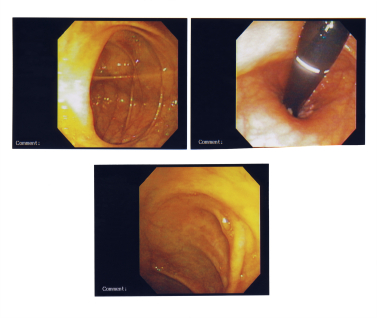

Процедура изображение ниже толстой кишки с тонкой, освещенная труба называется sigmoidoscope. Сообщения для диагностики причин диареи, воспалительные заболевания кишечника, такие как болезнь Крона или неспецифический язвенный колит, рак толстой кишки и других условий.